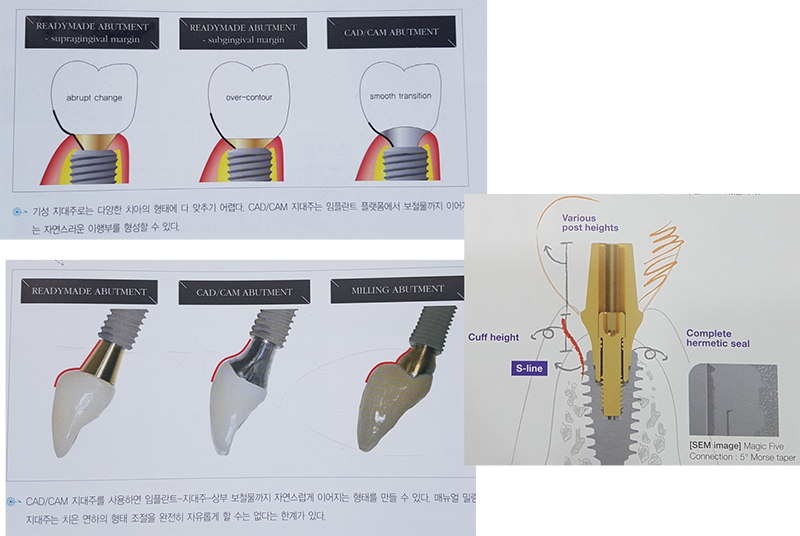

메가젠

임플란트의 어벗먼트가 갖는 S-line이면 족하다고

생각한다.

MegaGen의 S-line

cuff design을 좋아합니다